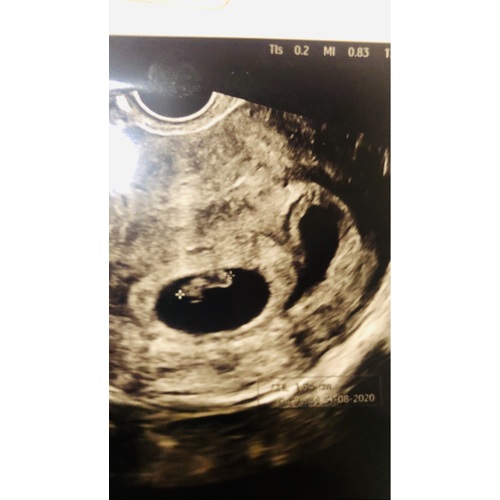

Dames ik denk dat ik hier op het juiste topic ben beland ! Ik heb een echo gehad alles prima 🙏🏼 na afloop zei ze kimberley, ik ga toch nog eens kijken of het er geen 2 zijn ? ! Hmmm ok want mijn vk is niet van dat twijfelende type ! Nee 1 Bebe prima 👌 boekje niet meer opengedaan tot s avonds voor de echo klaar te leggen voor mijn man 🤯 heel vreemd ik denk toch echt 2 vruchtzakjes te zien ! En mijn blaas is het niet , gevraagd aan de HA

Herkennen jullie dit ? Dank je om eens te kijken

( vk is in verlof tot dinsdag en moet sowieso op echo donderdag )